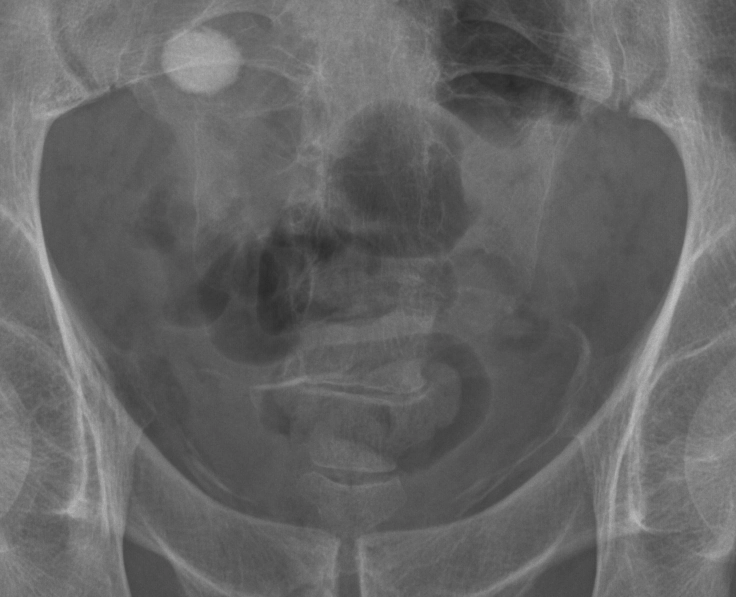

Sán máng bàng quang (Schistosomiasis urinary tract manifestations)

16/03/2026